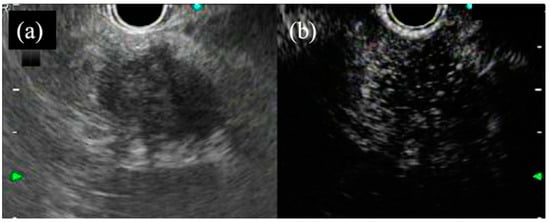

- Kida, M.; Kawaguchi, Y.; Miyata, E.; Hasegawa, R.; Kaneko, T.; Yamauchi, H.; Koizumi, S.; Okuwaki, K.; Miyazawa, S.; Iwai, T.; et al. Endoscopic ultrasonography diagnosis of subepithelial lesions. Dig. Endosc. Off. J. Jpn. Gastroenterol. Endosc. Soc. 2017, 29, 431–443. [Google Scholar] [CrossRef]